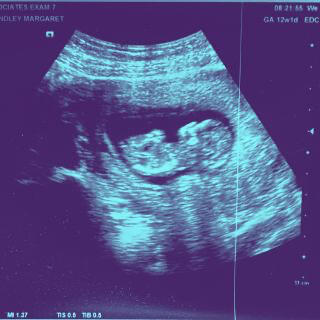

While visiting Brooklyn, an impromptu test in the 12 Chairs bathroom came back positive. We were cautiously superstitious and slow to celebrate—so for a while, we didn’t talk about Bruno.